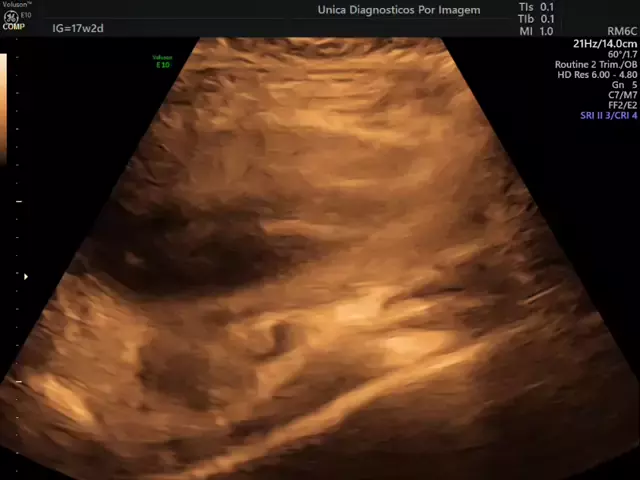

ultrassom 4D obstetrico.